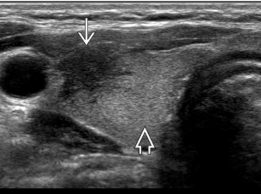

Identify each structure

Describe its US appearance + location in relation to the thyroid

1. Strap muscles (anterior/ thin hypoechoic band)

2. Sternocleidomastoid m. (lateral/ oval hypoechoic)

3. Longus colli m.(posterolateral/ triangle)

4. Trachea (posterior midline/ air shadow)

5. Esophagus (posterior to left lobe/ target)

6. CCA (lateral)

7. IJV (lateral